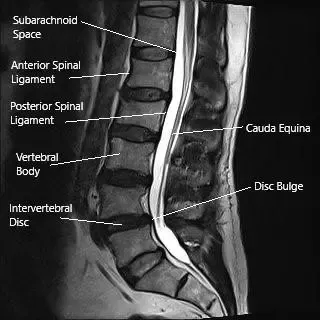

MRI of the lumbar spine in the sagittal section showing disc bulge.

The intervertebral disc consists of three parts:

- Annulus fibrosus: A tough, fibrous outer layer.

- Nucleus pulposus: A soft, gel-like center that absorbs shock.

- Endplates: Thin cartilage layers attaching the disc to the vertebrae.

Discs separate and cushion the vertebrae while allowing movement. When a disc prolapses or herniates, the displaced material can irritate or compress nerve roots within the spinal canal, causing pain and neurological symptoms.